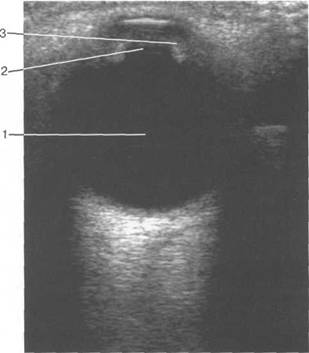

При сонографии отчетлив 121h711b о выявляется чивается хрусталиком, а сбоку - ресничным

четлив 121h711b о дифференцировать зрительный нерв и глазодвигательные мышцы (рис. 2.16, 2.17).

нии 10-15 мм от склеры (рис. 2.21,